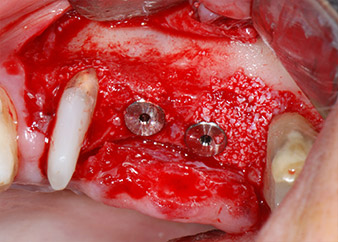

A continuación, los implantes (Restore, Keystone Dental, 3,75 mm de diámetro, 8,0 mm de longitud) se colocaron con el motor de implantes (figuras 11 y 12).

Las deficiencias óseas alrededor de los implantes, en el área mesial de la pieza 27 y alrededor de la raíz bucal de la pieza 24, se obturaron con partículas sustitutas de hueso xenógeno (Geistlich Bio-Oss) y se cubrieron con una membrana de colágeno absorbible (Geistlich Bio-Gide) a efectos de realizar un aumento mediante GBR

(figuras 13 y 14).